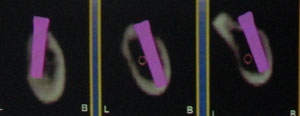

右上の写真はCT画像を基づいた、理想的なインプラント植立位置のシミュレート図です。オレンジのラインがアゴの神経の走行位置、紫色がプラントの植立予定位置です。右側のインプラントと比べると、長いインプラントが植立出来るのが分かります。

右下の写真はアゴの骨の断面図を示しています。同様にオレンジ色がアゴの神経の位置、紫色がインプラントの予定位置です。アゴの神経を損傷することなく、インプラントが植立出来るのが分かります。